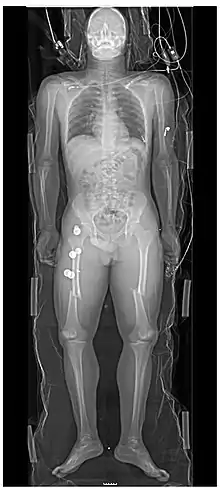

Whole body radiograph of traumatic injuries notable for fractures of both femurs (thigh bones), indicating major trauma

Persons with major trauma commonly have chest and pelvic x-rays taken,[6] and, depending on the mechanism of injury and presentation, a focused assessment with sonography for trauma (FAST) exam to check for internal bleeding. For those with relatively stable blood pressure, heart rate, and sufficient oxygenation, CT scans are useful.[6][25] Full-body CT scans, known as pan-scans, improve the survival rate of those who have suffered major trauma.[26][27] These scans use intravenous injections for the radiocontrast agent, but not oral administration.[28] There are concerns that intravenous contrast administration in trauma situations without confirming adequate renal function may cause damage to kidneys, but this does not appear to be significant.[25]